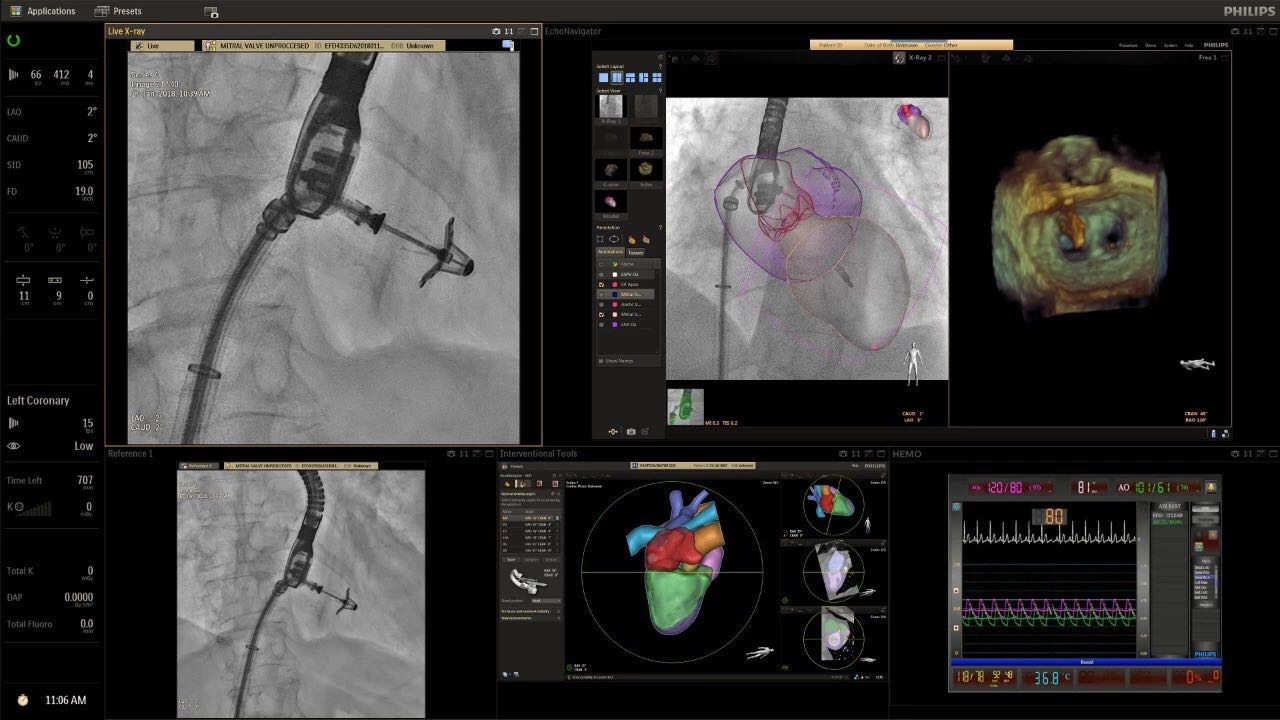

在日益復(fù)雜的干預(yù)期間,臨床醫(yī)生需要快速、輕松地可視化關(guān)鍵解剖結(jié)構(gòu)并確定手術(shù)過(guò)程中患者的變化。2019年1月17日,飛利浦宣布推出采用FlexArm的Azurion 7 C20,旨在提高圖像引導(dǎo)程序的定位靈活性。

帶有FlexArm的Azurion 7 C20 包含一系列創(chuàng)新技術(shù),使臨床醫(yī)生可以更輕松地在整個(gè)患者身上進(jìn)行二維和三維成像。當(dāng)臨床醫(yī)生移動(dòng)系統(tǒng)時(shí),圖像光束自動(dòng)保持與患者的對(duì)準(zhǔn),允許更一致的可視化并使他們能夠?qū)⒆⒁饬性谥委熒稀?/span>

飛利浦表示,采用FlexArm設(shè)計(jì)的Azurion 7 C20可提供卓越的靈活性和直觀的控制。該系統(tǒng)由智能運(yùn)動(dòng)引擎驅(qū)動(dòng),可在八個(gè)不同的軸上移動(dòng),所有這些軸均由其單個(gè)“Axsys”控制器控制。臨床醫(yī)生的模擬測(cè)試表明,該系統(tǒng)有可能顯著減少患者,工作人員和設(shè)備的重新定位,從而改善微創(chuàng)手術(shù)的可及性,包括通過(guò)患者手腕進(jìn)入身體的手術(shù)(橈動(dòng)脈入路),并降低患者的風(fēng)險(xiǎn)。無(wú)意中拔出電線和管子,以及節(jié)省大量時(shí)間。該系統(tǒng)非常適合混合手術(shù)室(OR),可滿足一個(gè)房間內(nèi)的多種專業(yè)需求,例如手術(shù)和血管內(nèi)手術(shù)的組合。

FlexArm在不少于8軸的情況下旋轉(zhuǎn),從而創(chuàng)建幾乎無(wú)限的靈活性來(lái)執(zhí)行成像,從頭部到腳部在左側(cè)和右側(cè)進(jìn)行2D和3D可視化。圖像光束保持與患者對(duì)齊,允許在旋轉(zhuǎn)或角度期間更好地可視化解剖結(jié)構(gòu)。使用Axsys運(yùn)動(dòng)控制系統(tǒng)輕松操作支架。